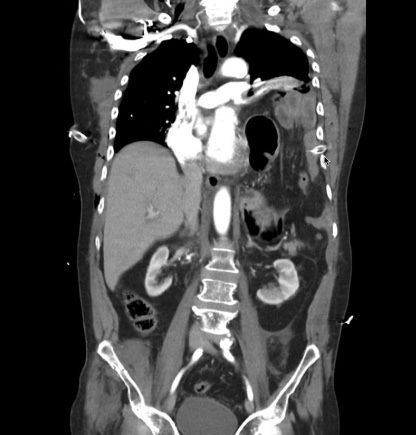

Rupture de l’Hémidiaphragme

- Aspect d’hémothorax mais localisé

- Perte de la coupole

- Parfois visualisation de l’estomac, angle colique